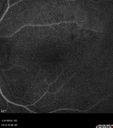

Diabetic Macular Ischemia - Enlarged FAZ - OCT-A613 views70 year old female diagnosed with diabetes 2 years ago. Her blood pressure was normal at 116/73. She has vision loss for 6 months in both eyes. VA is 20/100 OU. OCT-A shows macular ischemia.Apr 02, 2020

Diabetic Macular Ischemia - Enlarged FAZ - OCT-A465 views70 year old female diagnosed with diabetes 2 years ago. Her blood pressure was normal at 116/73. She has vision loss for 6 months in both eyes. VA is 20/100 OU. OCT-A shows macular ischemia.Apr 02, 2020

Diabetic Macular Ischemia - Enlarged FAZ - OCT-A379 views70 year old female diagnosed with diabetes 2 years ago. Her blood pressure was normal at 116/73. She has vision loss for 6 months in both eyes. VA is 20/100 OU. OCT-A shows macular ischemia.Apr 02, 2020

Diabetic Macular Ischemia - Enlarged FAZ - OCT-A377 views70 year old female diagnosed with diabetes 2 years ago. Her blood pressure was normal at 116/73. She has vision loss for 6 months in both eyes. VA is 20/100 OU. OCT-A shows macular ischemia.Apr 02, 2020

Diabetic Macular Ischemia - Enlarged FAZ - OCT-A365 views70 year old female diagnosed with diabetes 2 years ago. Her blood pressure was normal at 116/73. She has vision loss for 6 months in both eyes. VA is 20/100 OU. OCT-A shows macular ischemia.Apr 02, 2020

Diabetic Macular Ischemia - Enlarged FAZ - OCT-A446 views70 year old female diagnosed with diabetes 2 years ago. Her blood pressure was normal at 116/73. She has vision loss for 6 months in both eyes. VA is 20/100 OU. OCT-A shows macular ischemia.Apr 02, 2020

Diabetic Macular Ischemia - Enlarged FAZ - OCT-A395 views70 year old female diagnosed with diabetes 2 years ago. Her blood pressure was normal at 116/73. She has vision loss for 6 months in both eyes. VA is 20/100 OU. OCT-A shows macular ischemia.Apr 02, 2020

Diabetic Macular Ischemia - Enlarged FAZ - OCT-A368 views70 year old female diagnosed with diabetes 2 years ago. Her blood pressure was normal at 116/73. She has vision loss for 6 months in both eyes. VA is 20/100 OU. OCT-A shows macular ischemia.Apr 02, 2020

Diabetic Macular Ischemia - Enlarged FAZ - OCT-A426 views70 year old female diagnosed with diabetes 2 years ago. Her blood pressure was normal at 116/73. She has vision loss for 6 months in both eyes. VA is 20/100 OU. OCT-A shows macular ischemia.Apr 02, 2020

Diabetic Macular Ischemia - Enlarged FAZ - OCT-A477 views70 year old female diagnosed with diabetes 2 years ago. Her blood pressure was normal at 116/73. She has vision loss for 6 months in both eyes. VA is 20/100 OU. OCT-A shows macular ischemia.Apr 02, 2020

Diabetic Macular Ischemia - Enlarged FAZ - OCT-A432 views70 year old female diagnosed with diabetes 2 years ago. Her blood pressure was normal at 116/73. She has vision loss for 6 months in both eyes. VA is 20/100 OU. OCT-A shows macular ischemia.Apr 02, 2020